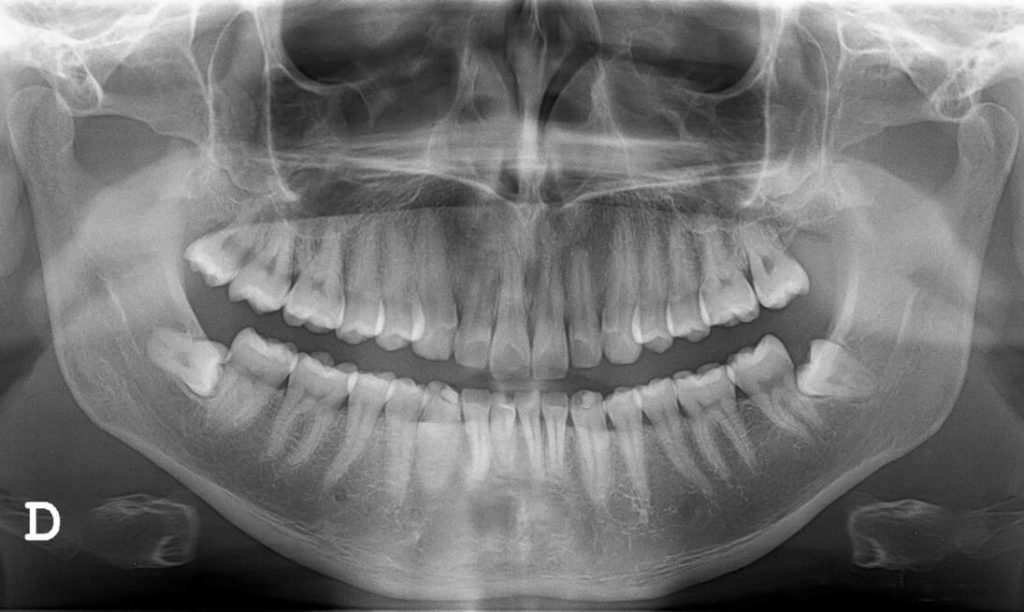

zahnfreilegung retinierte zähne

Für eine Retention gibt es verschiedene Ursachen. Oft befinden sich die Zähne nicht an ihrer richtigen Position im Kiefer. Manchmal entwickeln sie sich auch mit einer Achsabweichung und liegen schief im Knochen. Derart verlagerte Zähne können Druck auf die Zahnwurzeln der Nachbarzähne ausüben und diese so gefährden. Von Retention und Verlagerung sind häufig die Eckzähne, die seitlichen Backenzähne (Prämolaren) und die Weisheitszähne betroffen.

Retinierte Weisheitszähne im Oberkiefer - Röntgenbild

Röntgenbild eines retinierter Weisheitszahns

Eine Röntgenaufnahme und ein Tastbefund verschaffen dem Zahnarzt einen ersten Überblick über die genaue Lage des retinierten, teilretinierten und/oder verlagerten Zahnes. Besonders genau werden die Zahnstrukturen, der Verlauf des Unterkiefernervs und das umliegende Gewebe mit dreidimensionalen Röntgenaufnahmen (DVT) dargestellt. Diese bilden auch die Grundlage für die Planung des Eingriffs.